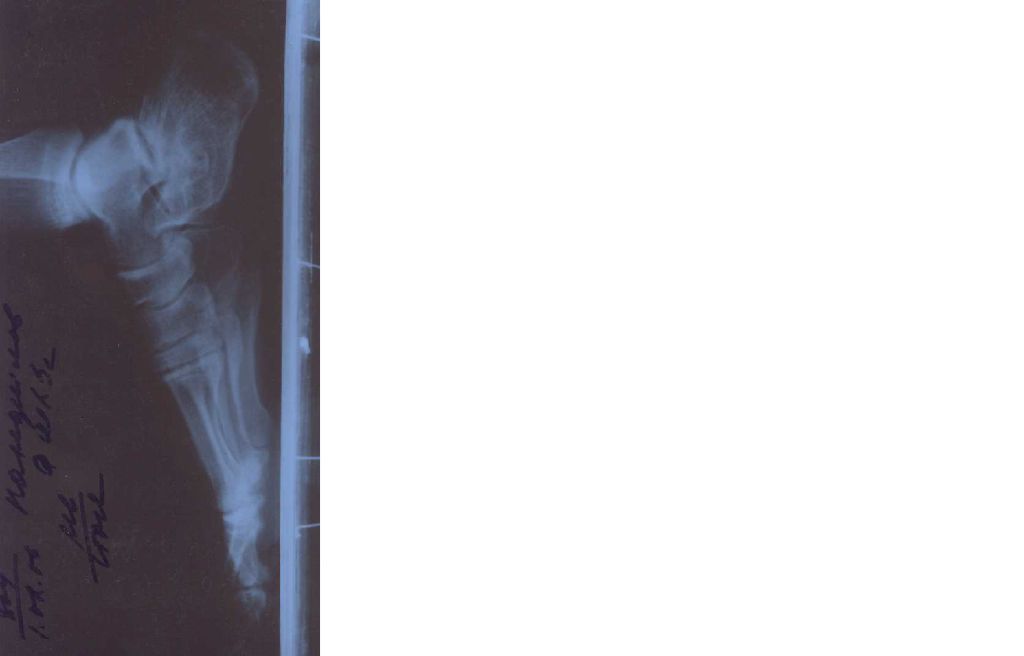

после перелома пяточной кости со смещением развился артроз в таранно-пяточном суставе.Хотел пойти на артродез, но есть мнения против...

Здравствуйте!в январе 2004 г. упал с высоты.в местном петрозаводском травмпункте наложили гипс-сапожок, на контрольном снимке спустя неделю уточнили диагноз, направили в Горбольницу, где произвели репозицию (несильно надавили руками) и гипс до паха на четыре месяца. После снятия гипса две недели ходил на процедуры-парафинотерапия.Для лучшей информированности о моем заболевании проконсультировался в нескольких местах- НИИ Вредена и в Республиканской больнице- за прошедшее за все это время.В институте мне объяснили, что рано или поздно придется делать операцию-артродез таранно-пяточного сустава, и я почувствую, когда придет время исходя из своих болевых ощущений. Не скажу, что за прошедшие четыре года в моих болевых ощущениях много изменилось-по-прежнему время от времени и в зависимости от нагрузок они проявляются, и моя подвижность ограничена, иногда, редко, во время ходьбы приходится останавливаться, чтобы переждать приступ боли- просто хотелось наконец решить окончательно этот больной вопрос оперативно, и забыть.Но на след консультации в Республиканской больнице, на которую я пошел, чтобы укрепить свою решимость, мне посоветовали не торопиться, отложить операцию "до последнего", а пока полечиться консервативно: операция сложная, возможны осложнения, нет гарантий, что уйдут болевые ощущения, можно будет восстановить былую физ. активность (ранее занимался спортом)Не будет ли такая отсрочка просто потерей времени, оттягиванием неминуемого оперативного вмешательства?

• Кликните для загрузки файла рентгенограмма от 01.02.06.jpg

25KB (25784 bytes)